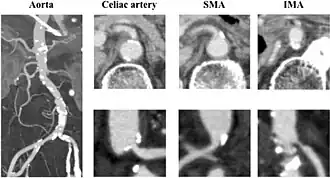

Enhanced computed tomography showing severe atherosclerosis of the arteries. The aorta shows broad calcifications, and the celiac artery shows moderate stenosis, although the lumen of the superior mesenteric artery was relatively patent. In addition, stenosis of the inferior mesenteric artery was very severe.

Abdominal angina is caused by obstruction or stenosis of the inferior mesenteric artery (IMA), celiac trunk, or superior mesenteric artery (SMA).[4] More than 95% of abdominal angina is caused by stenosis of the splanchnic arteries due to local atherosclerosis.[5][6] The occlusion mainly affects the ostia or the last few centimetres of the mesenteric arteries.[7]